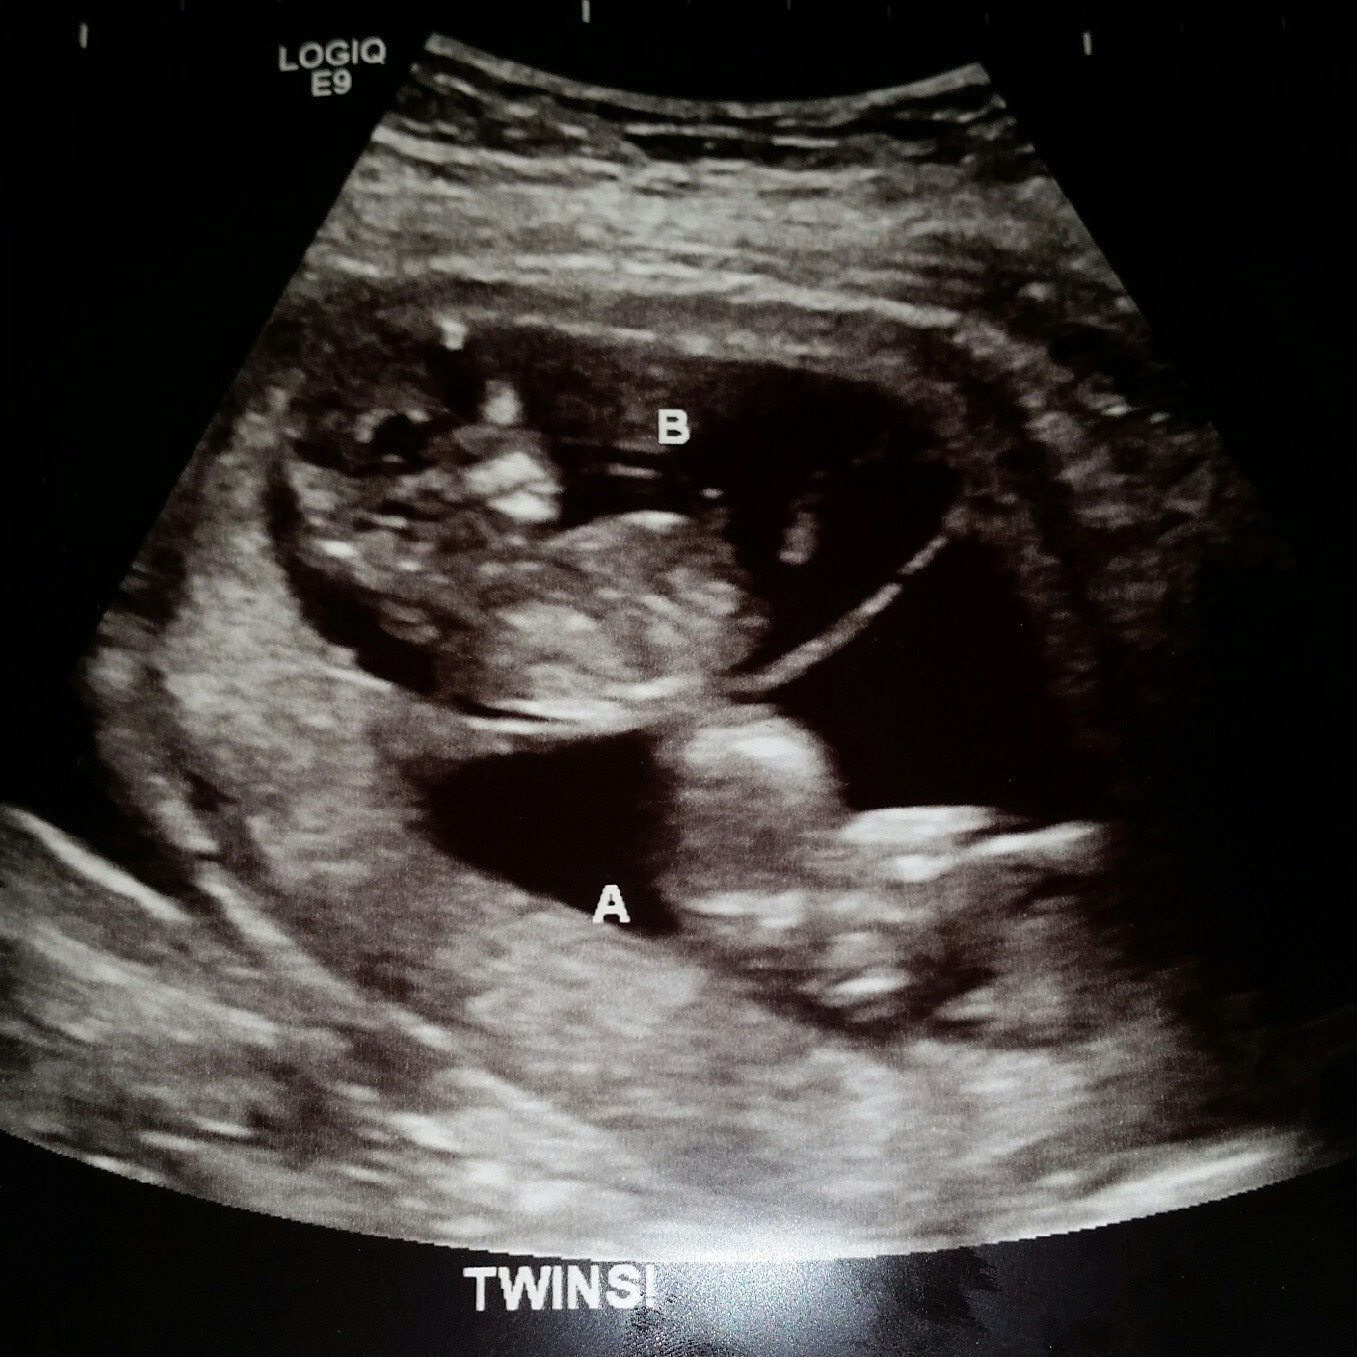

Ultrasound Photos at 12 Weeks Pregnant With Twins